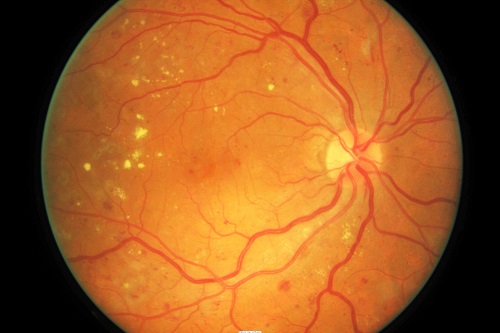

§ 糖尿病患者

糖尿病伴随着各种各样的并发症,其中就包括糖尿病性视网膜病变。建议糖尿病患者应在确诊后进行眼底检查,无病变者或病变轻的每年进行复查,病变严重者每3个月进行一次眼底检查。

▲糖尿病性视网膜病变